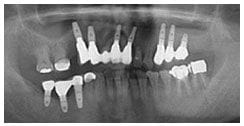

X 光片

術前X光片

術後X光片